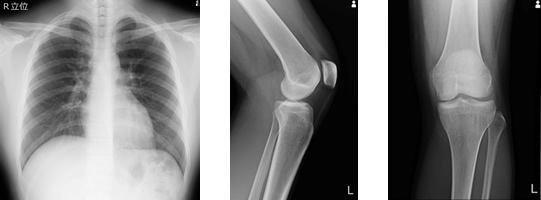

一般撮影

一般撮影とは、俗にいうレントゲン撮影のことです。X線を照射して胸やお腹、全身の骨などの透過像を撮影し、胸部(肺や心臓)の異常影、腹部の腸管ガス・結石など病気のおおまかな状態や骨折などを把握出来ます。当院では2018年12月からほぼ全てFPD(フラット・パネル・ディテクタ)システムで撮影を行い被ばくの低減に努めています。

運動器カテーテル治療は、「モヤモヤ血管」と呼ばれる異常な血管による慢性的な関節痛を改善する治療法で、具体的には「経カテーテル微細動脈塞栓術(TAME)」という治療方法です。この治療では、カテーテルを挿入し、薬剤でモヤモヤ血管を塞ぐことで痛みを軽減します。使用する薬剤は安全性が高く、全身麻酔を使わず、負担が少ないのが特徴です。この治療は、従来の方法で改善が難しかった慢性関節痛に効果的ですが、現時点では保険適用外で、治療費は全額自己負担となります。詳細は担当医にご確認ください。